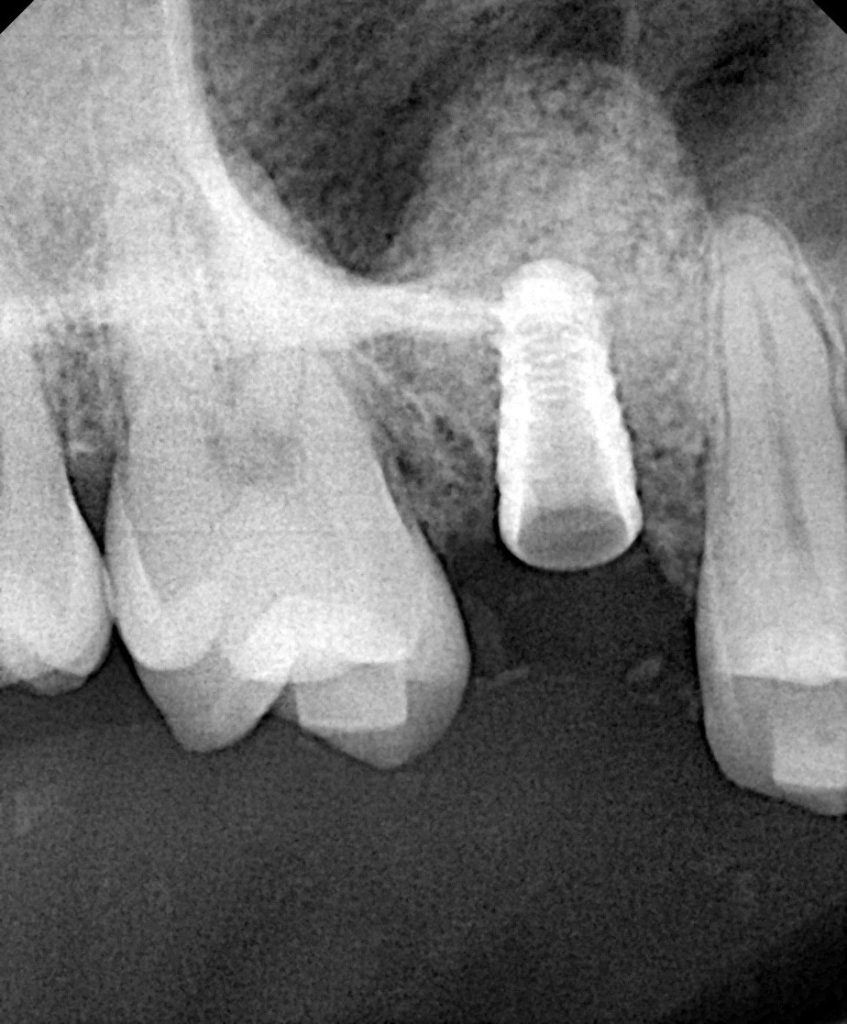

After verifying intact sinus membrane integrity via the Valsalva maneuver, particulate bone graft (allograft + synthetic blend) was incrementally packed into the osteotomy using osteotomes (Fig 3). Approximately 2 mm of membrane elevation was achieved beyond the sinus floor without perforation.